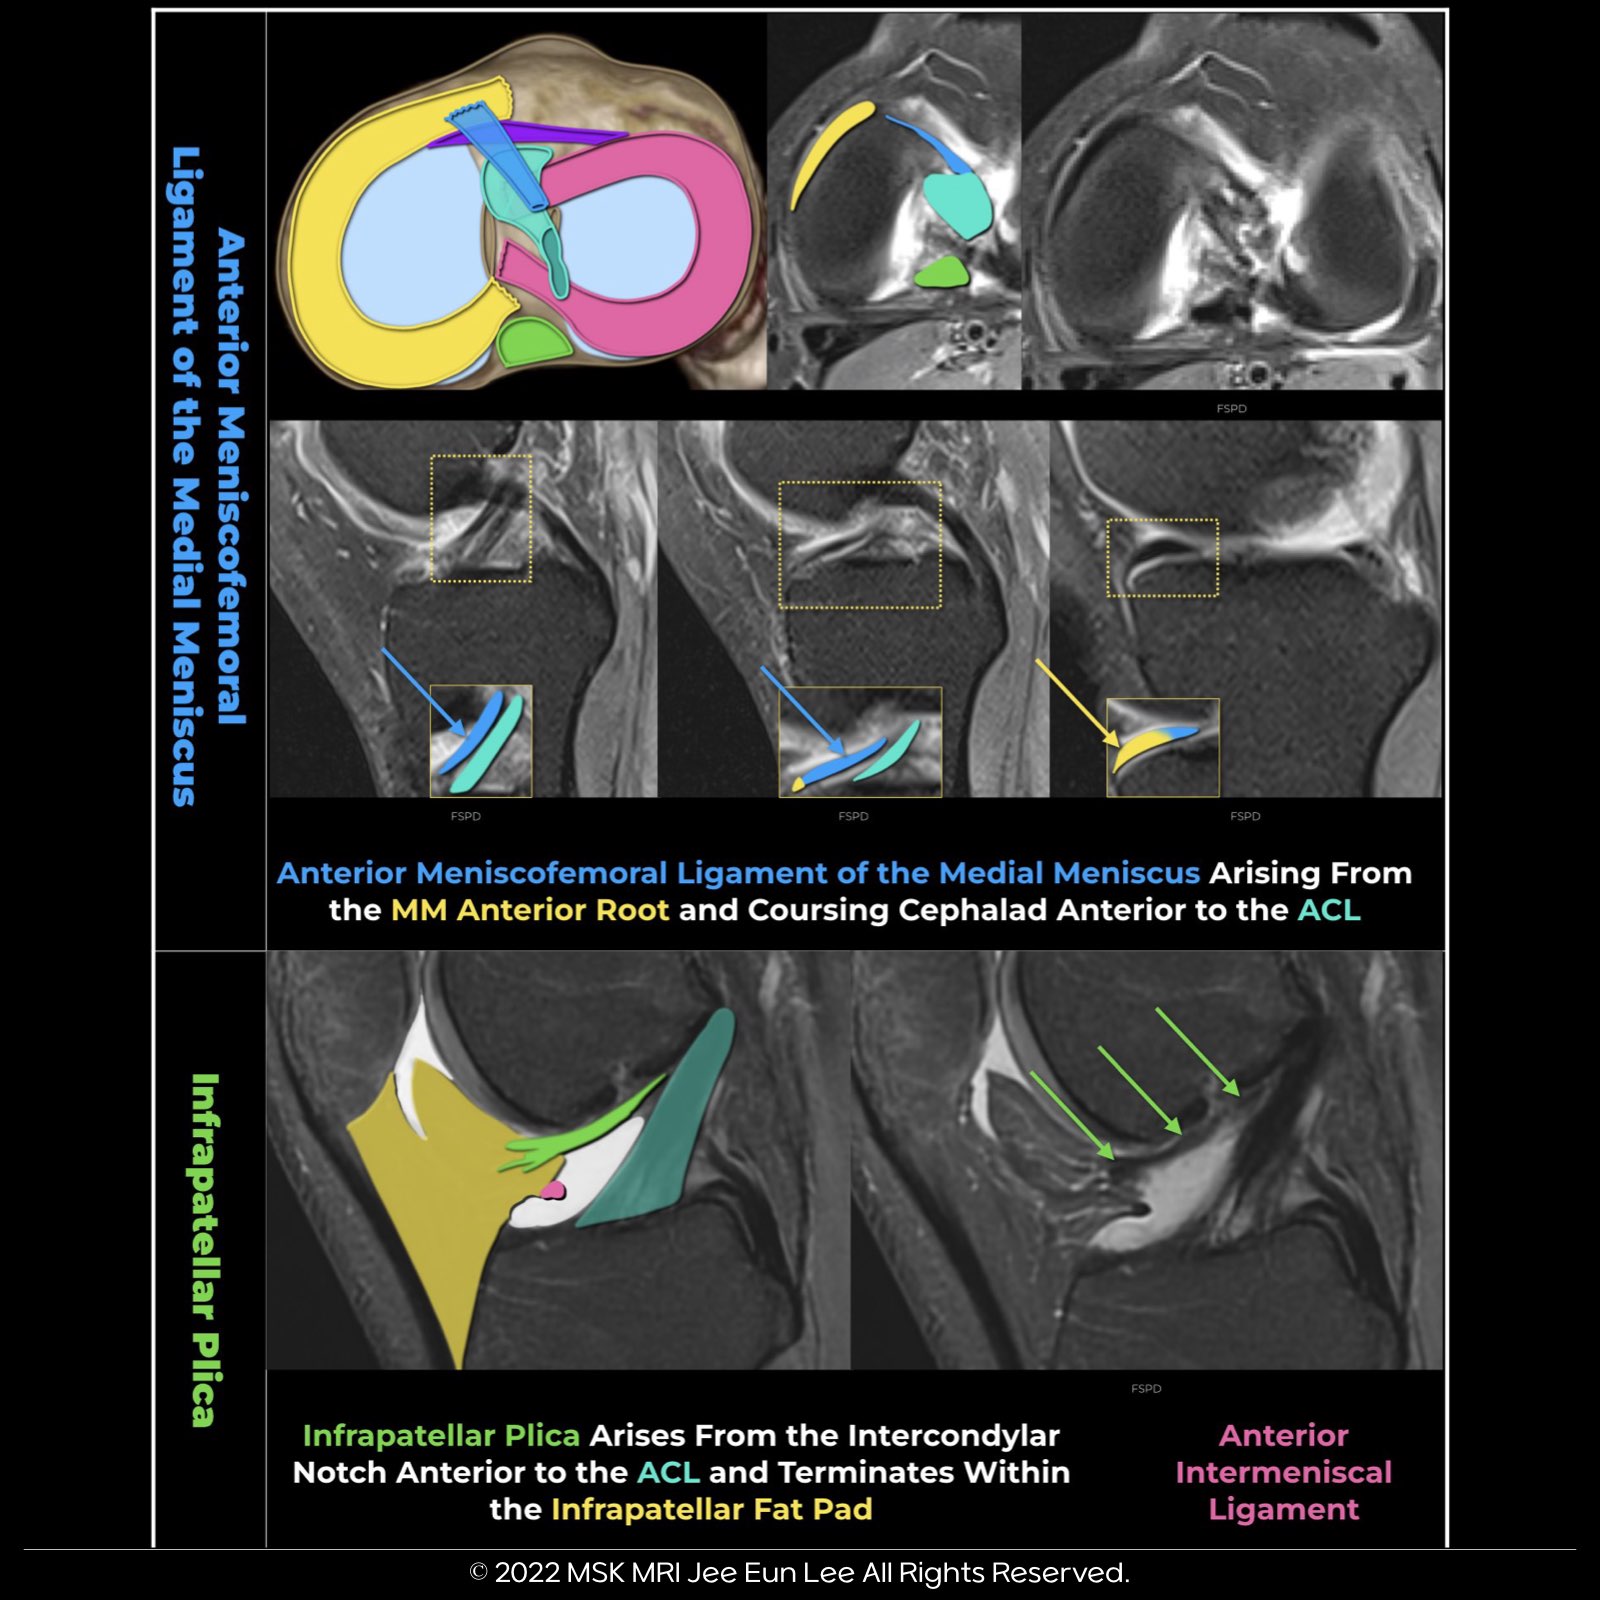

https://youtu.be/kEuMzUrHD0M"Anomalous insertion of the medial meniscus (AIMM) into the anterior cruciate ligament (ACL) is an uncommon condition, seen in about 0.52% of arthroscopy cases. It involves a ligament extending to the ACL from the anterior horn of the medial meniscus, near the root.

This variant accessory insertion appears on sagittal proton density–weighted MRI images as a fibrous strand connecting the anterior horn to the ACL. It's important to distinguish this anomaly from an ACL tear, a meniscal tear, or an infrapatellar plica in MRI interpretations.

The anterior meniscofemoral ligament, found in this condition, runs parallel and posterior to the ligamentum mucosum and attaches anteriorly to the ACL. It looks similar to the infrapatellar plica but is more medially located and doesn't extend into the infrapatellar fat pad.

The infrapatellar plica, or ligamentum mucosum, starts at the anterior intercondylar notch and runs anteroinferiorly, curving up to the lower pole of the patella. When both the anterior meniscofemoral ligament of the medial meniscus and the infrapatellar plica are present, the former lies parallel to and posterior to the ligamentum mucosum."